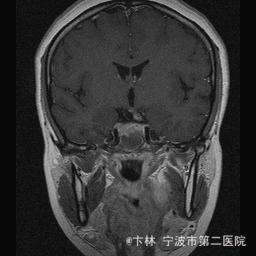

40岁女性,因“双眼视力下降三月余伴停经1个月余”入院。 患者三月前无明显诱因下出现双眼视力下降,视物模糊,尤以左眼为甚,只能近距离看到手动,无头痛、头晕,无恶心、呕吐,无视物旋转,无行走困难等不适,患者曾在某眼科医院就诊治疗,考虑为双眼视神经炎,予以营养,补液对症等治疗(具体不详),情况不见好转,近一月来患者月经停止,来我院神经外科门诊,予以查头颅CT,头颅MRI,提示“垂体大腺瘤”,为求进一步治疗收住入院

予以完善血,尿,粪常规检查,及凝血功能全套,输血功能全套及垂体功能全套,蝶鞍冠状CT等术前检查措施,行经蝶入路垂体瘤切除术。术后予以对症,补液,调节血电解质等治疗,患者视力明显改善,复查头颅MRI提示肿瘤基本全切,一周后患者出院。

此病人颅内垂体瘤体积较大,突破鞍隔压迫视交叉,故患者视力视野障碍为首发症状,该肿瘤主体有大部分向蝶窦腔生长,因此采用经蝶手术入路,肿瘤切除满意,术后患者视力视野恢复满意,。